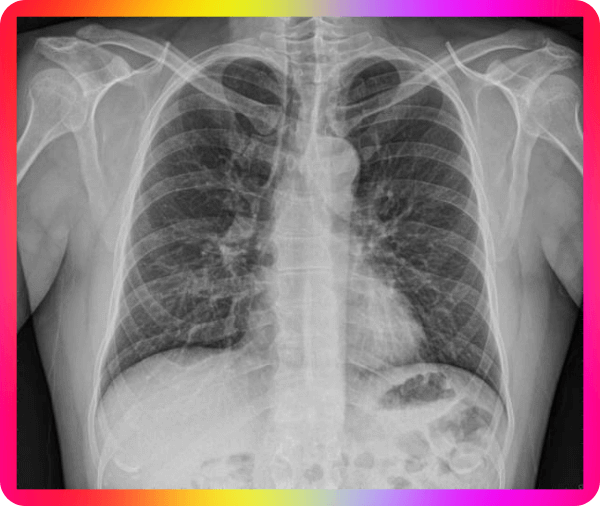

가래가 지속이 되는 경우 피가 섞여 나오게 되면 걱정이 되는데요 이런 경우 어떻게 해야 할지 난감해집니다. 가래 피가 섞여 나오면 혈담이라고 하고, 가래보다 혈액이 많으면 객혈이라고 하는데요 세균에 감염이 된 경우는 누렇거나 초록색에 가까워진다고 하는데요 반드시 흉부 CT촬영을 통해 검사를 받는 것이 좋다고 합니다.

피가 섞여 나오는 경우 의심하는 질환 종류는 위에서 언급된 기관지 염증, 후두염, 결핵, 폐암, 기관지 확장증, 혈관 문제 등을 의심을 해야 한다고 하며 가래가 갑자기 많이 나오거나 가래가 끓어서 호흡곤란, 고열, 색깔이 진해지는 경우, 녹색으로 변하는 경우, 악취가 느껴지는 경우는 꼭 병원 내방이 필요한 경우라고 합니다.